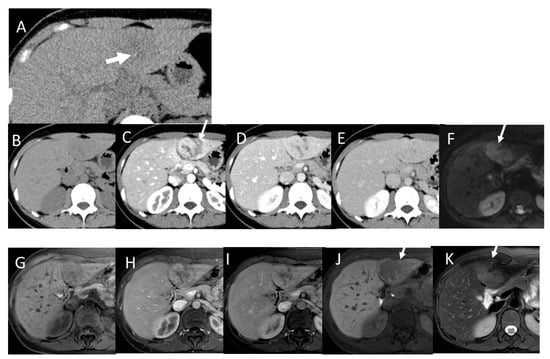

4.2. Early Hepatocellular Carcinoma (Early-HCC)

4.3. Well-Differentiated Hepatocellular Carcinoma (Well-HCC)